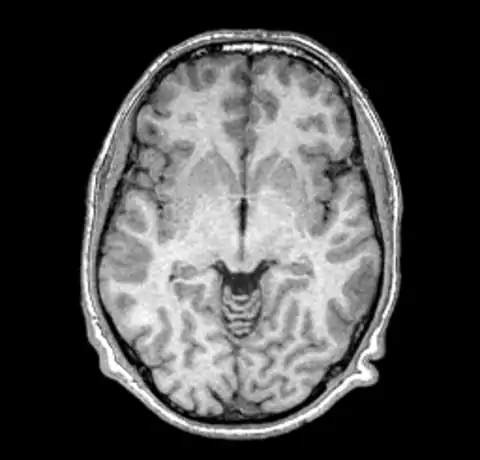

B0 non-uniformity is difficult to detect when simply looking at images without the assistance of a judiciously ranged color map. In our test case we'll start with a simple T1 MPRAGE image from a 1.5T Siemens scanner.

The above image and all the images here were created using mincpik in a similar fashion to the below.

Note that it is difficult to pick the non-uniformity in the image unless you look carefully at the intensity of the white matter in the lower parts of the image. In order to correct this image we run nu_correct with the default parameters.

We can now take a look at the corrected file (out.mnc)

As it is very hard to pick the differences between the original and corrected version we can create a field image to visualise the differences.

And then for completeness sake, here are the original and corrected image using a spectral colormap to better visualise the change. Note that in the second (corrected) image the intensity of the white matter is more uniform (the red part).